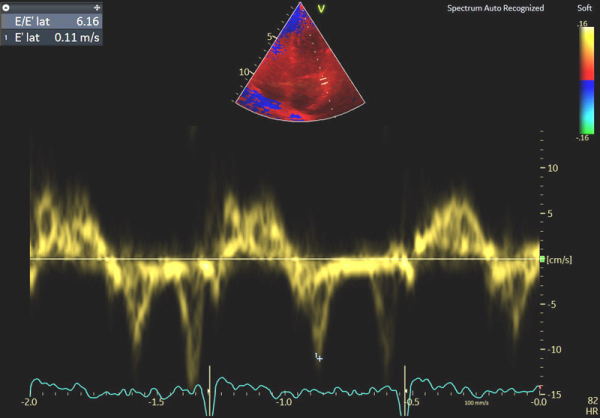

Image 4 : échocardiographie Doppler tissulaire à l’anneau mitral latéral

En cas d’atteinte précoce d’amylose cardiaque, ce sont en effet les premières anomalies à pouvoir être objectivées et il peut ne pas y avoir encore d’altération marquée du SLG (cf Image 7), de signe de dysfonction diastolique VG (cf Images 3 et 4), de dilatation de l’OG (cf Image 8), de dysfonction systolique du VD (cf Image 5) et les pressions peuvent être normales.